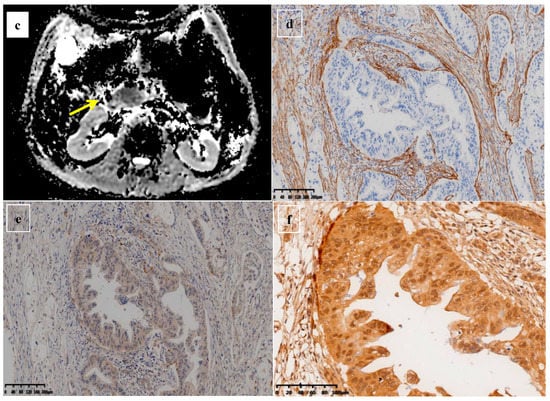

Figure 4.

A 58-year-old woman was found to have a tumor with a head size of about 2.2 cm in the pancreas, which was pathologically confirmed to be pancreatic ductal adenocarcinoma after surgery; we found that the tumor was characterized by a high ADC value, high D value, and low f value after quantitative MRI measurement. She survived for 61 months without recurrence after surgery. MRI T2 (a); DWI (b); and ADC map (c) showed solid mass in the head of pancreas with measured ADC of 1.59 × 10−3 mm2/s, D value of 1.41 × 10−3 mm2/s, and f value of 0.18. Immunohistochemical staining showed that a few cancer-associated fibroblasts (CAFs) were present in the stroma ((d) α-SMA, ×10), carcinoma cells weakly expressed VEGF in the cytoplasm ((e) VEGF, ×10), and carcinoma cells showed weak immunoreaction of anti-HIF-1a in the nuclear((f) HIF-1α, ×20). These findings suggested that the tumor microenvironment was relatively quiet with a lower hypoxia level.

Figure 5.

A 61-year-old man was found to have a tumor with a head size of about 2.1 cm in the pancreas, which was pathologically confirmed to be pancreatic ductal adenocarcinoma after surgery; we found that the tumor was characterized by a low ADC value, low D value, and high f value after quantitative MRI measurement. He was found to have a local recurrence at follow up 9 months after surgery and died 15 months later. MRI T2 (a), DWI (b), and ADC map (c) showed solid mass in the head of pancreas measured ADC measurements of 1.07 × 10−3 mm2/s, D value of 0.91 × 10−3 mm2/s, and f value of 0.47. Immunohistochemical staining showed an abundance of CAFs in the stroma ((d) α-SMA, ×10), carcinoma cells with higher expression of VEGF in the cytoplasm ((e) VEGF, ×10), and HIF-1a in the nuclear ((f) HIF-1α, ×20). These findings suggested that the tumor microenvironment was active with a higher hypoxia level.